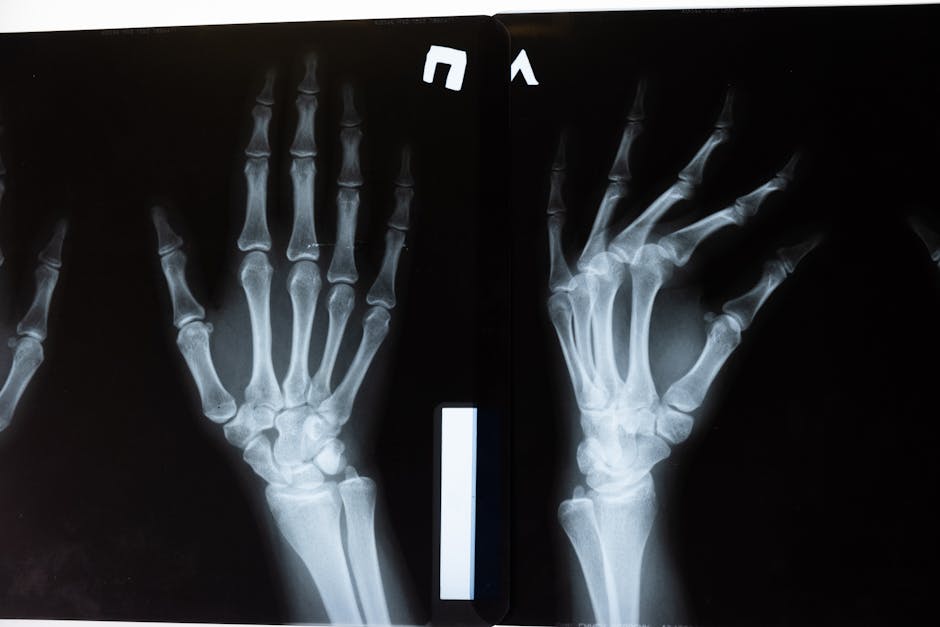

Breakthrough Discovery Reveals Key to Lifelong Bone Strength